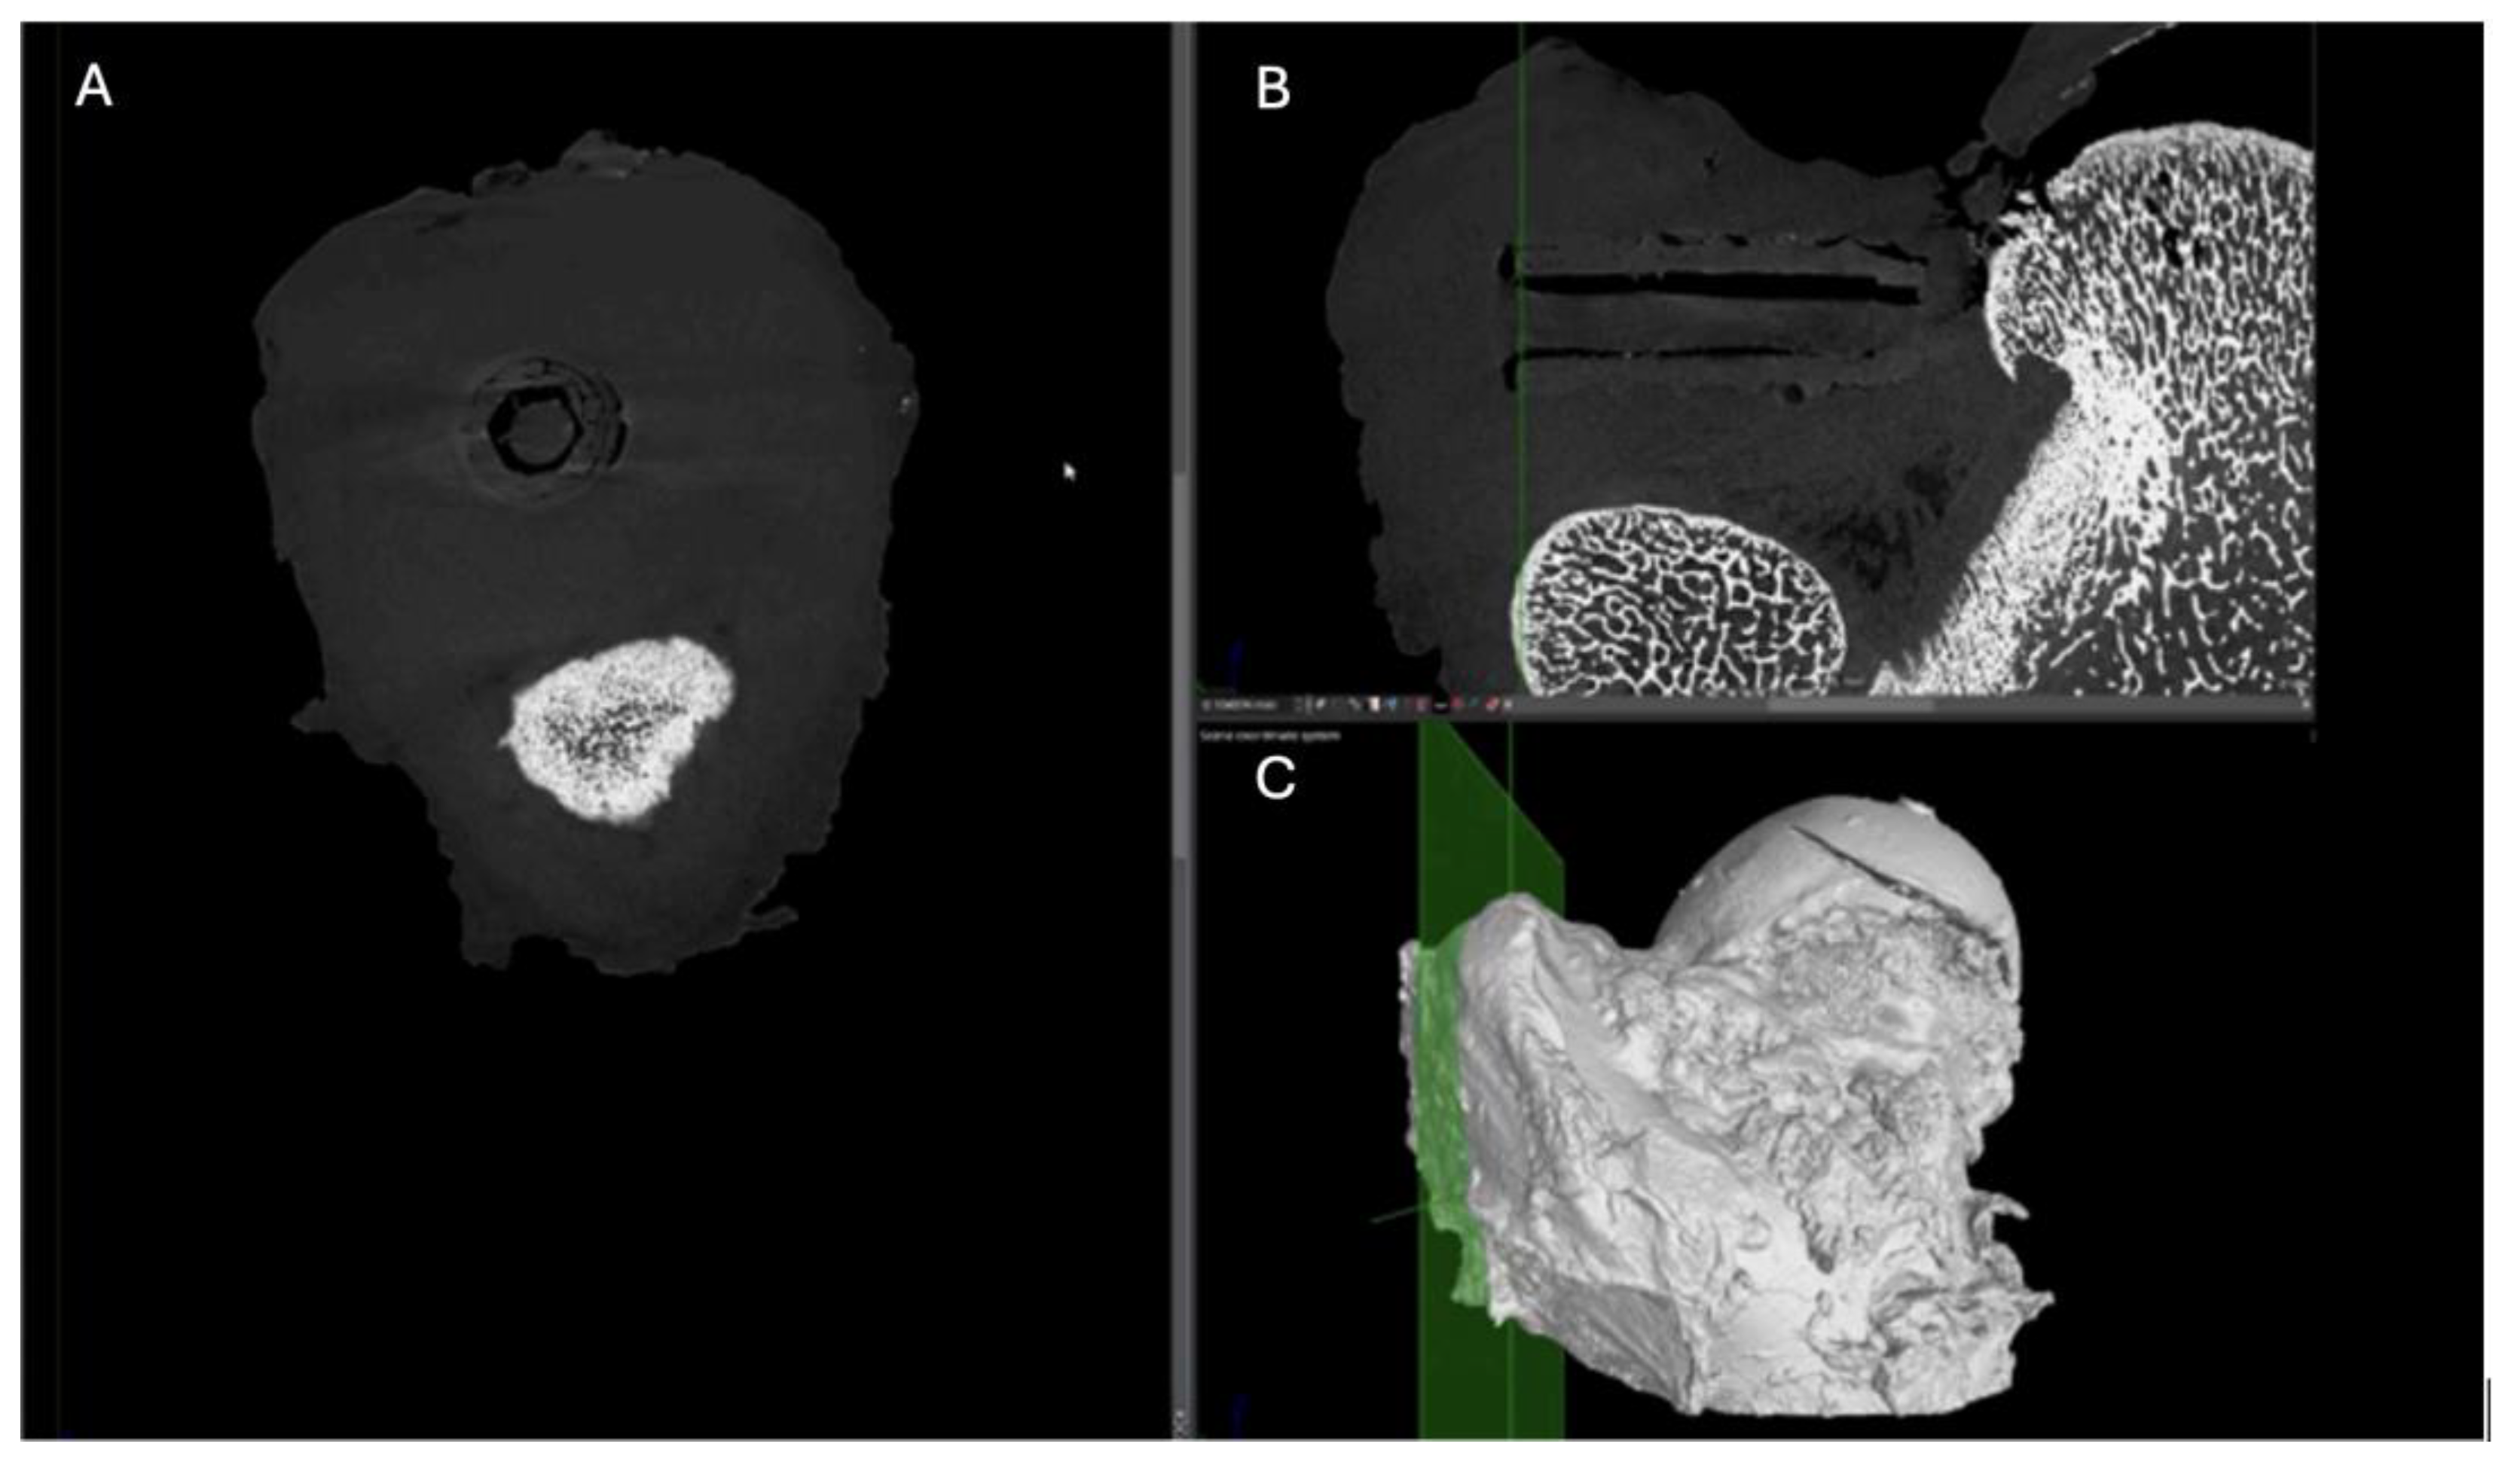

Figure 21. Computed tomography study of the left femur sample, fourth-month post-surgery, with PLA material. (A) axial, (B) sagittal reconstruction and(C) 3D imaging.

PLA: Partial view of the left femur in a pig at a four-month postoperative follow-up, assessed through axial slices, sagittal reconstruction, and 3D visualization. Across all images, hyperdense areas identified, indicating bone growth into the interior of the PLA screw. Additionally, there is a partial increase in circumferential density toward the distal third of the screw, suggesting proper osseointegration and bone formation. (Figure 21)

PEEK: In the tomographic study at the fourth postoperative month, the polymer screw (PEEK) is observed following a lateralised trajectory within the medullary canal. In the sagittal and transverse projections, the femoral bone exhibits preserved structural integrity. However, suboptimal trabecular coverage is noted, particularly at the lateral and distal ends of the screw. While the proximal end shows adequate trabecular apposition, the mid to distal regions display insufficient bone integration, especially at the tip of the screw. This suggests a limited osteointegration response in those areas.

The overall bone response indicates mild biocompatibility, with sparse trabecular formation and minimal new bone coverage in the affected zones. Additionally, a few small gas bubbles are visible in the adjacent soft tissues, without signs of significant inflammatory reaction. These findings support a predominantly fibrointegrative rather than osteointegrative pattern at this stage of evaluation. (Figure 22)